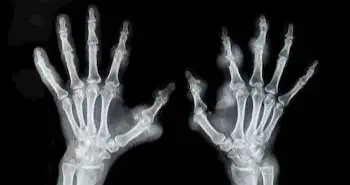

Autoantibody Status is not found to be associated with early treatment response to first-line MTX in patients with early RA

The relationship between autoantibody status and treatment response to methotrexate (MTX) remains unclear in RA.

The relationship between autoantibody status and treatment response to methotrexate (MTX) remains unclear in RA. The researchers aimed to find an association between autoantibody status and early remission in recently diagnosed RA patients treated with MTX using real-world data.